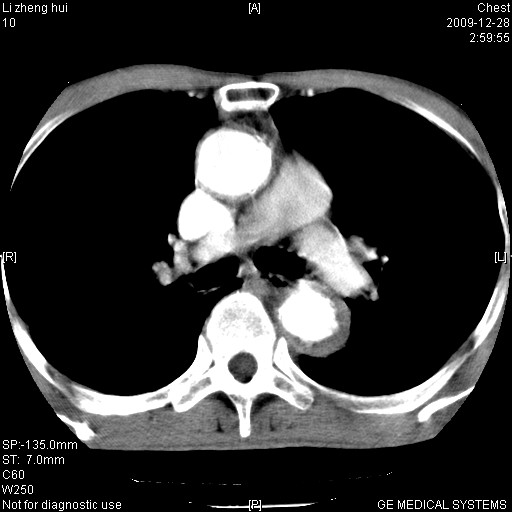

标题: CT23859:胸主动脉瘤

男  79岁 胸部痛急诊入院,晚上做的增强

考虑主动脉瘤?(增粗、钙化、壁血栓?)

支持降主动脉瘤,不考虑夹层

动脉瘤伴附壁血栓

1)考虑胸主动脉壁间血肿或夹层动脉瘤。2)多发性肝囊肿。

1)考虑胸主动脉附壁血栓或夹层动脉瘤。2)多发性肝囊肿。